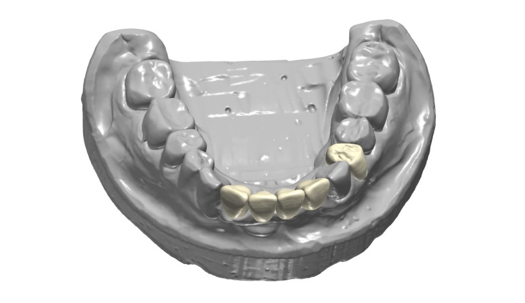

The next case follows the digital protocol for fully guided surgery and prosthetics. A CBCT radiograph, digital impression, and digital photography were the cornerstones to the success of this case. The 3D data set was electronically delivered to the dental laboratory. The data were merged and the process to develop the plan was initiated. The use of CBCT was essential in this case, particularly due to minimal space for placement of individual implants and single-unit crowns. The patient's chief concern was that she wanted to have single-unit crowns instead of fixed crown-and-bridge restorations because she was worried that she would someday find herself in an assisted-living facility; if that were to happen, she wondered, who would help floss under her bridge work? Her decision was to have single implants with individual crowns. CBCT technology is much more accurate in evaluating space maintenance and management.10 Periapicals in the past were rather close for calculating spacing; however, the CBCT identifies the buccal-lingual dimensions as well as the mesial-distal measurements. On review of the completed proposals for implant placement and provisionals, it was determined that there was sufficient spacing for implant placement to allow appropriate emergence profiles for the provisionals and then eventually the final single-unit cemented crowns. The proposal was accepted, and a 3D-printed surgical stent was fabricated, along with the PMMA provisionals (Figure 29 through Figure 35).

Fig 31. Digital diagnostic wax-up.

Figure 31

Fig 32. Digital provisional proposals.

Figure 32

Fig 33. CBCT imaging merged with scanned impressions.

Figure 33

Fig 34. Implant placement proposal.

Figure 34

Fig 35. Digital proposal of the surgical guide.

Figure 35